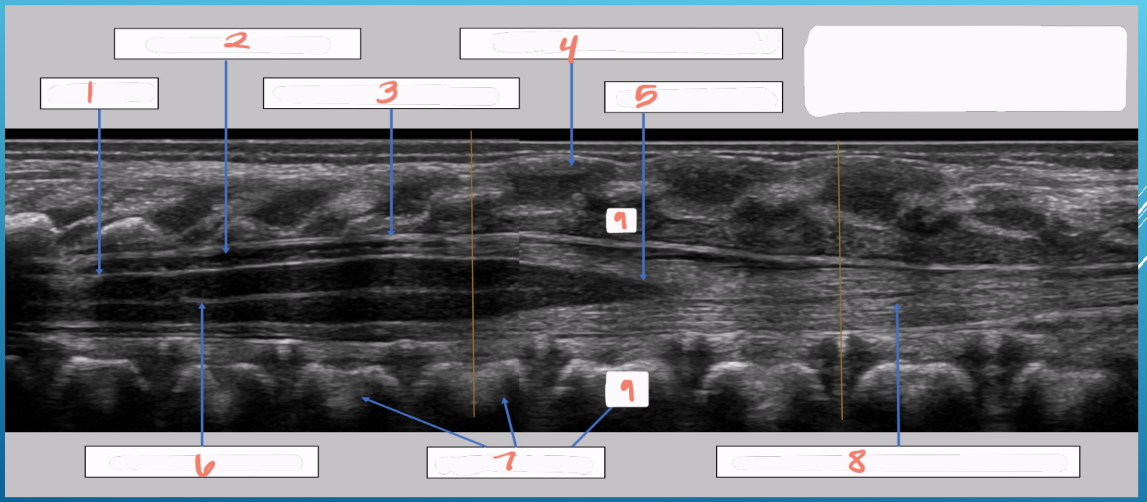

vb

vertebral bodies

d

intervertebral disks

p

spinous processes

arrowheads

arachnoid/dural layer

e

epidural space

*

subarachnoid space w/ CSF

sc

hypoechoic spinal cord